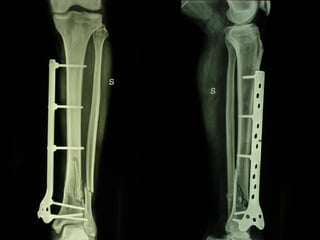

Dal Gennaio 2000 al Febbraio 2006 abbiamo trattato 167 fratture chiuse  con placca percutanea  in 164 pazienti :  27 lesioni diafisarie di gamba, 12 piloni tibiali ,  11 fratture prossimali di tibia, 36 fratture sovracondiloidee di femore, 17 fratture diafisarie di femore, 43 fratture metaepifisarie prossimali di omero, 21 diafisarie d’omero.  156 guarigioni 8 fallimenti

Dal Giugno 2002 al Dicembre 2004 abbiamo trattato 5 fratture esposte: 3 di tibia e 2 di ulna 5 guarigioni

I buoni risultati ottenuti dipendono da 5 punti fondamentali:   una accurata riduzione percutanea della frattura  precise vie di accesso  l’utilizzo della placca che consenta il più lungo braccio di leva possibile il pretensionamento della placca  una sintesi con un ridotto numero di viti